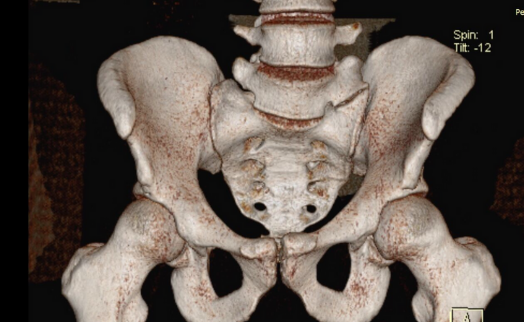

Między wyrostkiem kręgu L5 a kością krzyżową wytworzył się u niego dodatkowy staw poprzeczno-krzyżowy (typ 2a wg klasyfikacji Castellviego). Staw ten posiadał cechy stawu nieprawdziwego, czyli bez chrząstki, a więc występowało bolesne ocieranie kości o kość, utrudniające normalne funkcjonowanie.

W badaniach radiologicznych (zdjęcia rentgenowskie, tomograf komputerowy) uwidocznioną tę patologię, widać również obrzęk tych kontaktujących ze sobą powierzchni.